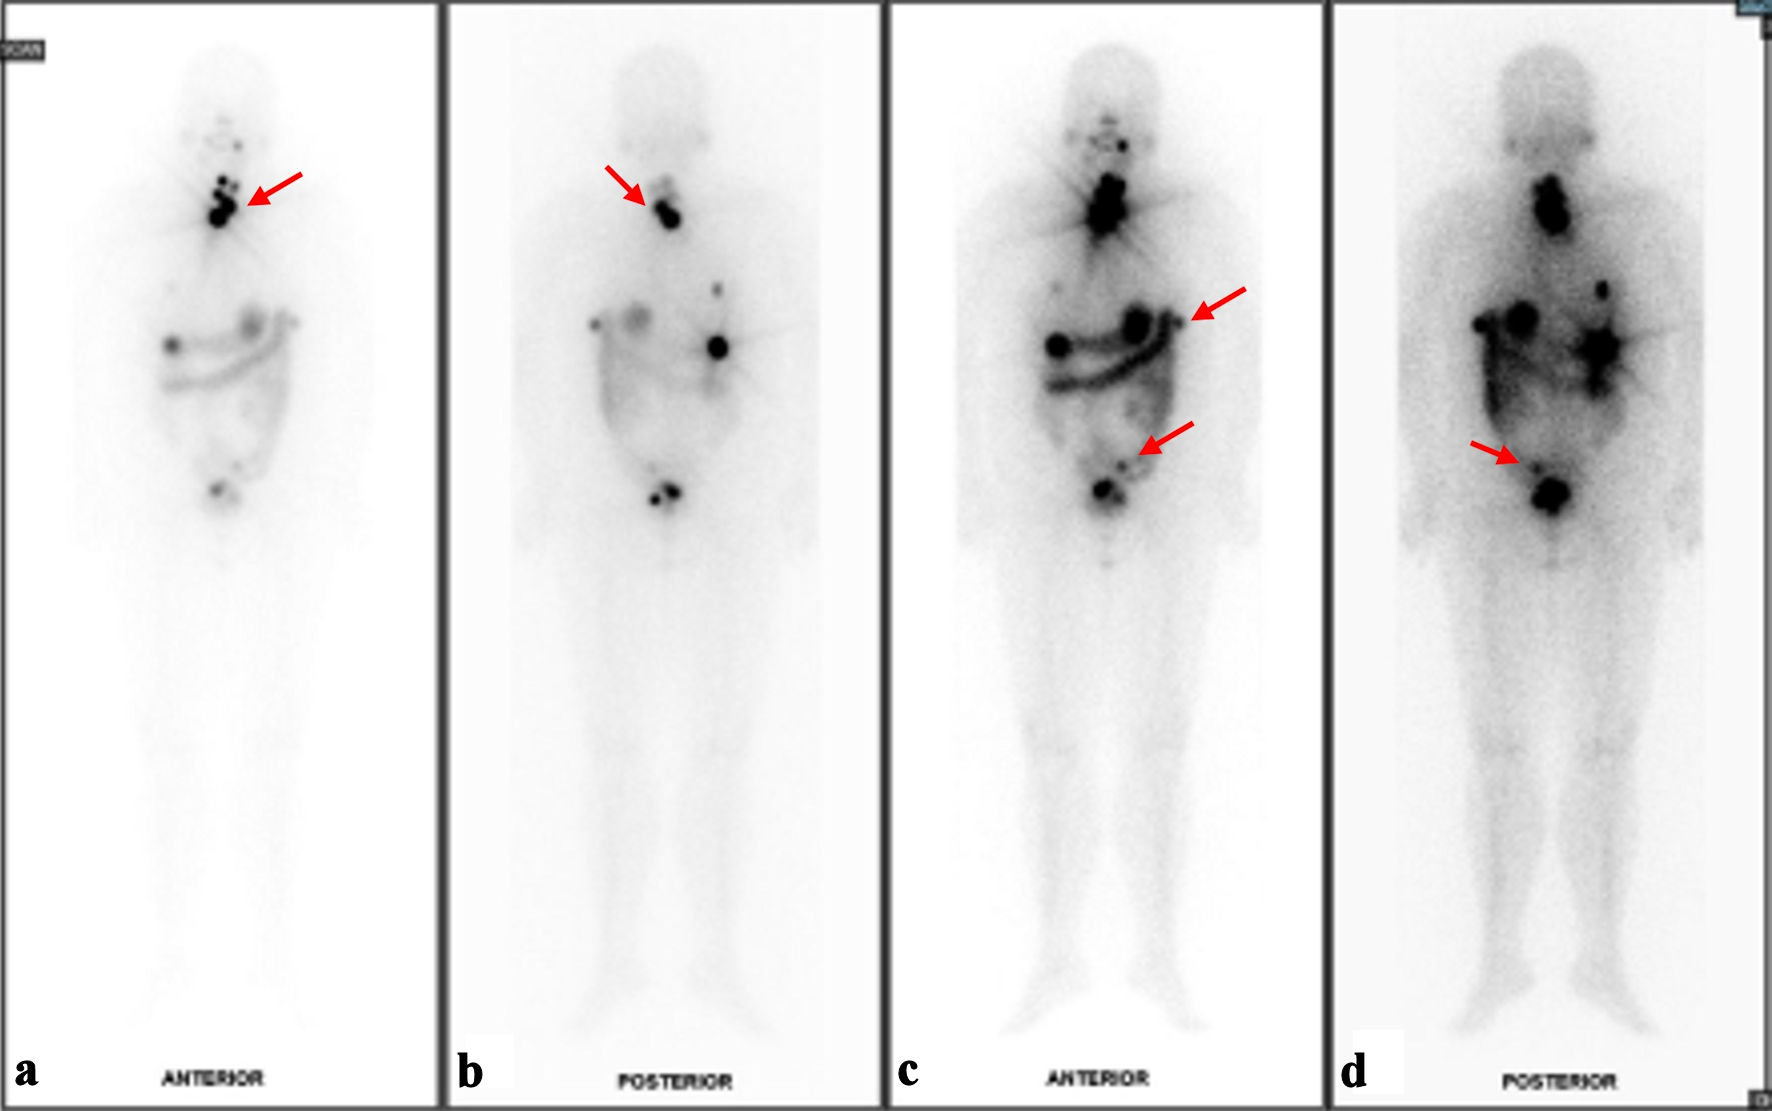

The next part of management was a total thyroidectomy and adjuvant radioiodine therapy. Furthermore, a second pathology was considered for the thyroid gland as an independent thyroid follicular neoplasm due to the difference in nuclear appearance on FNA. Repeat TG level 2 weeks postoperatively was already significantly lower at 117.1 µg/L. The patient underwent total thyroidectomy 2 months later. Histology of the thyroid gland showed classic-type multifocal papillary thyroid carcinoma (Fig. 2c, d), stage II T2N0M1, with no extension to skeletal muscle or adjacent structures and no lymphovascular invasion. She then underwent radioactive iodine (RAI) therapy with a dose of 150 mCi, and I131 whole body scan was performed 72 h post RAI (Fig. 3a-d). Prior to RAI, the TG level was 112 µg/L, anti-thyroglobulin (anti-Tg) was < 3.0 IU/mL, thyroid-stimulating hormone (TSH) was 60.86 pmol/L, and free thyroxine (FT4) was 5.6 pmol/L. The patient was doing well and had fully recovered from both surgeries. As discussed in a multidisciplinary meeting, the patient was scheduled to undergo imaging and laboratory tests every 6 months as surveillance. The patient has undergone CT of the abdomen and pelvis, as well as thyroid ultrasound, which have all been clear of disease, showing no residual nodules. Biochemical response has been monitored with TG, thyroid function tests and CA125, which have remained within normal since completion of treatment. She will continue long-term follow-up as there are reports of recurrence even 20 years after initial treatment [7].

Figure 3. Results of I131 whole body scan (WBS). (a) Foci of I131 uptake at the anterior neck likely represent remnant thyroid tissues although small volume disease cannot be ruled out on current baseline study (red arrow). (b) Posterior view of likely remnant thyroid tissues versus small volume disease (red arrow). (c) Several I131-avid foci in the upper abdomen and pelvic cavity with corresponding peritoneal nodules/nodularities are suspicious for residual disease (red arrows). (d) Indeterminate I131-avid focus at the sigmoid colon region (red arrow).